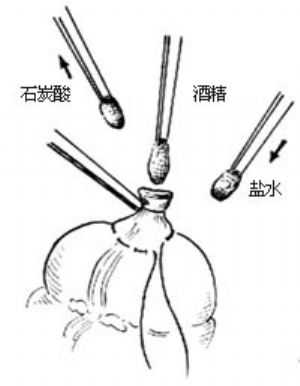

12.9 9.闌尾殘端處理

用3把尖端夾有小棉球的直止血鉗將棉球分別蘸上純石炭酸(或5%碘酊)、75%酒精和生理鹽水,依次在闌尾殘端粘膜面塗擦,然後棄去保護盲腸的鹽水紗布[圖1 ⑻]。

圖1 ⑻殘端消毒處理